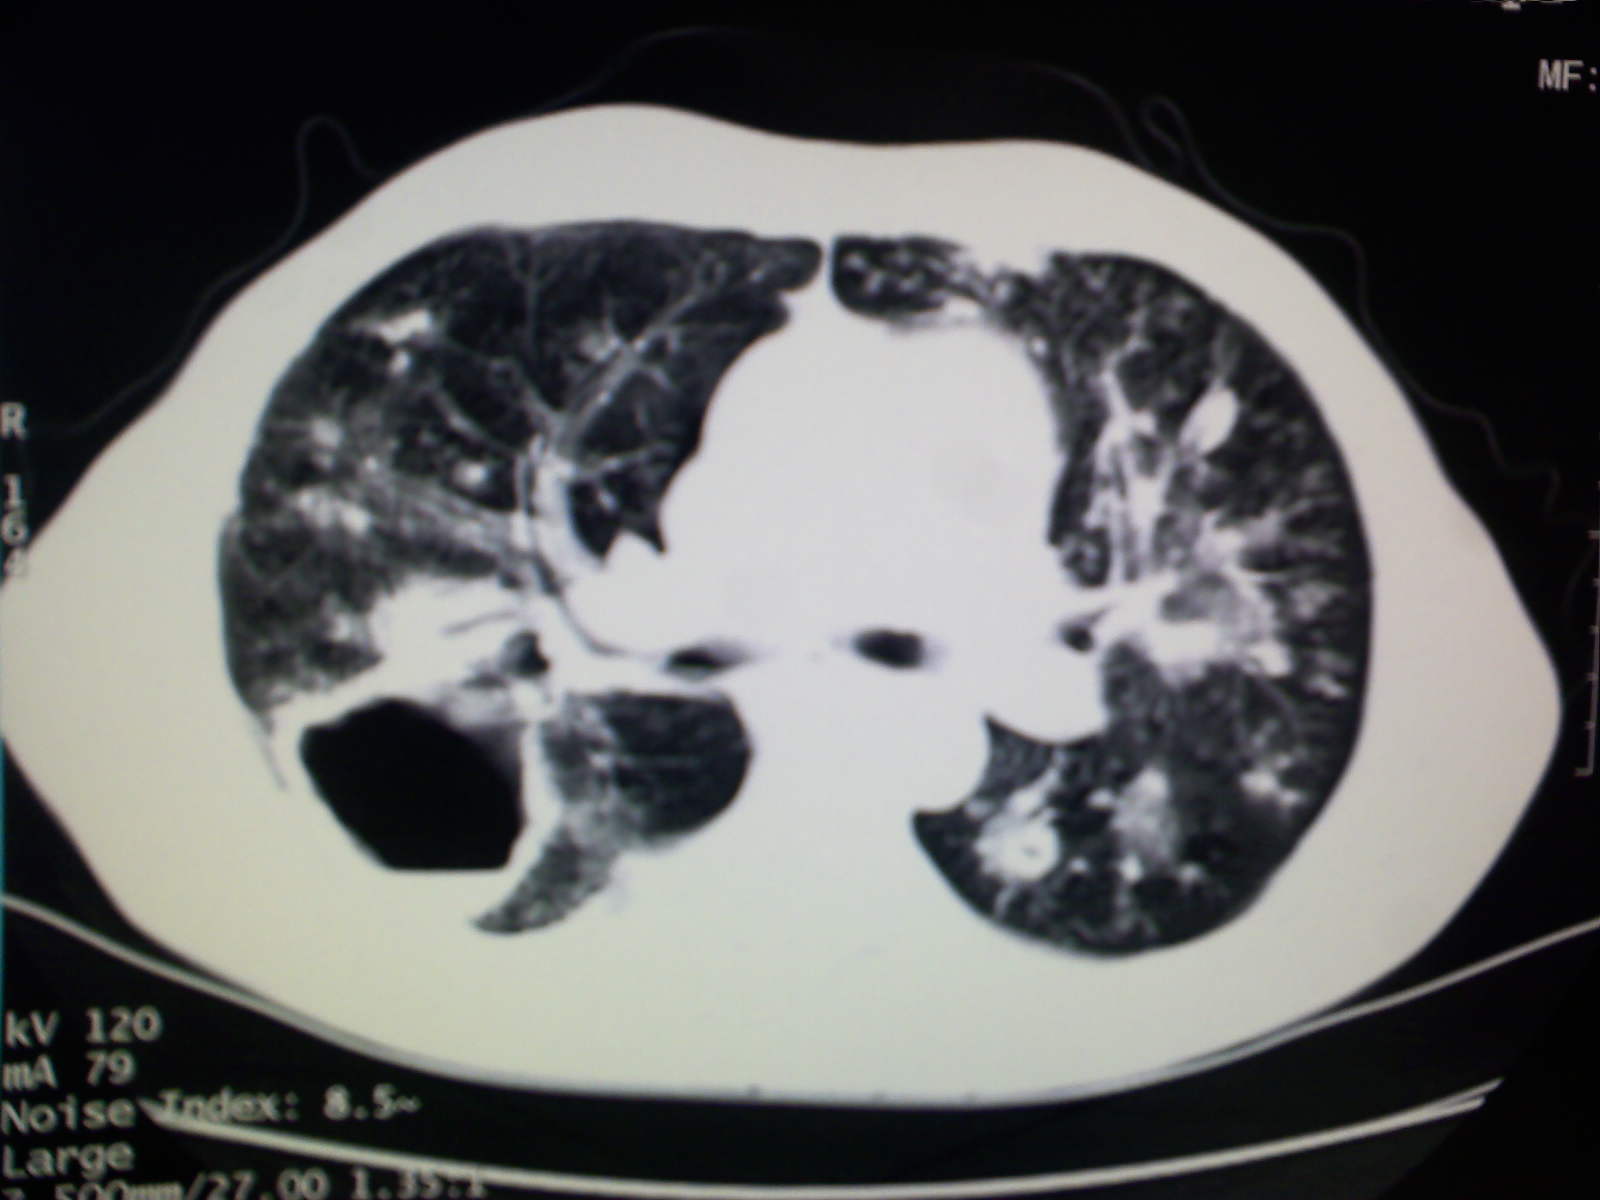

以下是引用卜一在2009-4-11 15:50:00的发言:[br]双肺继发性肺结核伴空洞形成,不排除合并霉菌感染!(病灶呈多形态 多特征 散在分布)。另:合并支气管扩张征伴感染!

以下是引用主力军在2009-4-11 15:55:00的发言:[br]两肺继发性肺结核可能性大。

以下是引用康鹏在2009-4-11 16:30:00的发言:[br]双肺继发性肺结核伴空洞形成合并感染[br]支气管扩张合并感染